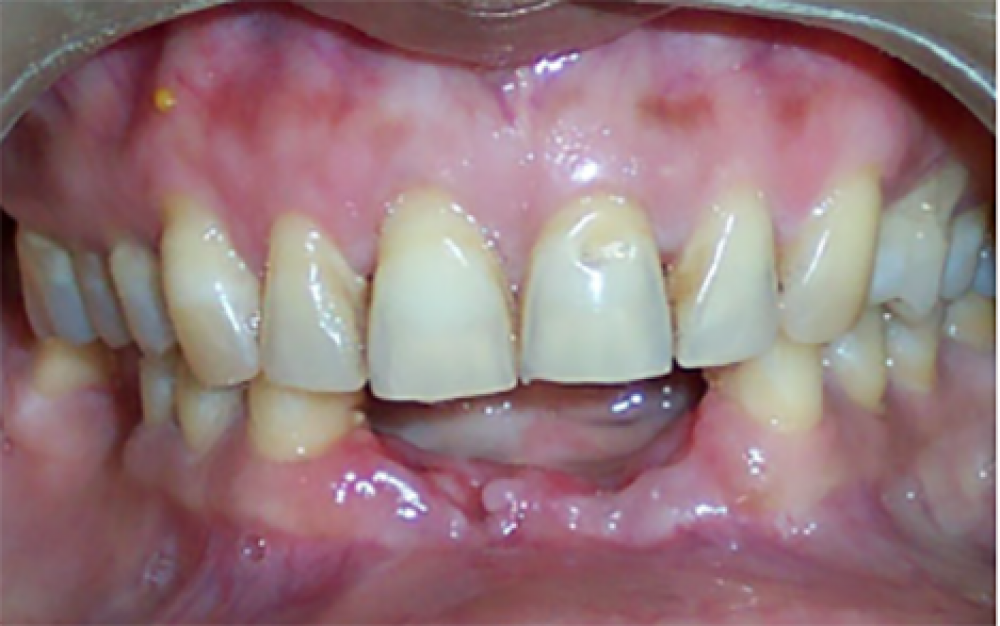

Before

After